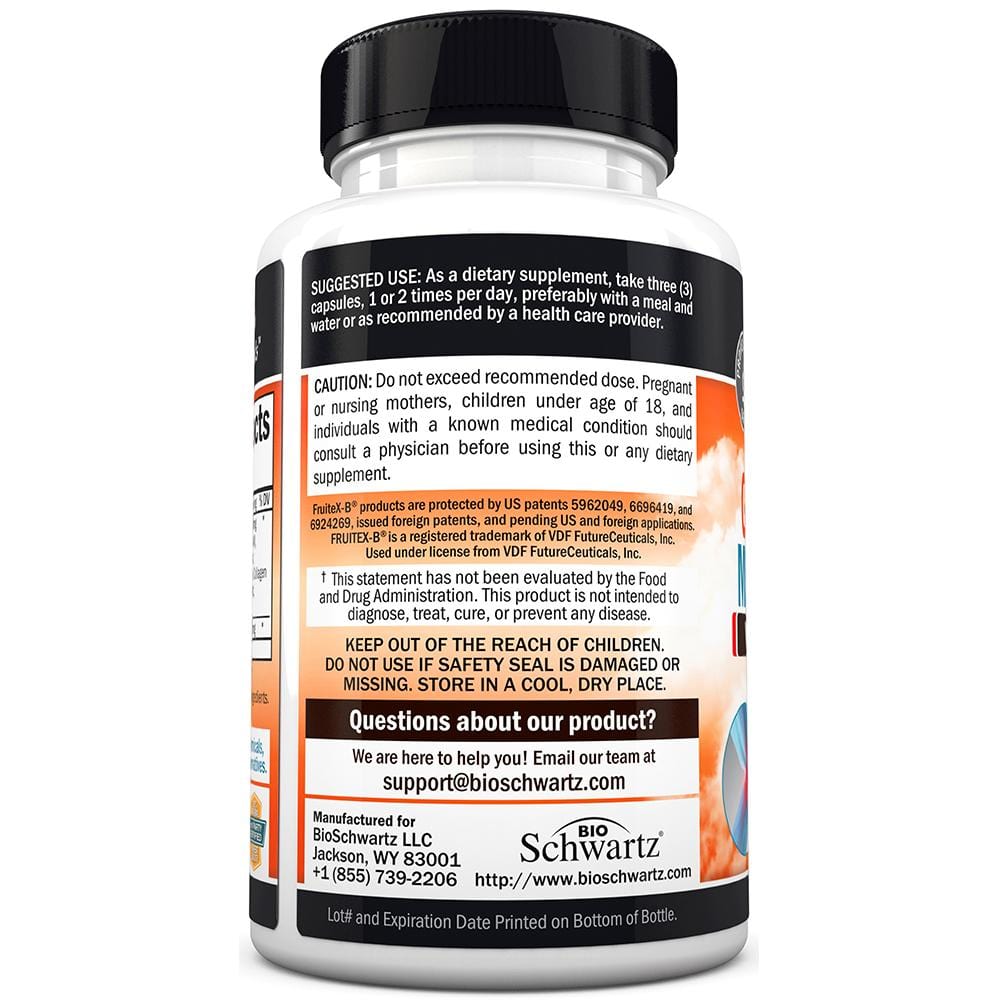

BioSchwartz Glucosamine MSM Chondroitin is formulated with a proprietary blend of 10 powerful ingredients, including Patented Fruitex-B, Boswellia Extract and Turmeric Curcumin to promote a healthy inflammatory response to easy discomfort and support mobility.†

This powerfully potent formula that helps to protect bones and provide the nutrients necessary to nurture healthy cartilage to maintain sound joint structure.†

We've combined Chondroitin Sulfate with Hyaluronic Acid and Hydrolyzed Collagen, two more components critical to proper joint lubrication and sustained mobility for maximum efficacy.†

BioSchwartz Glucosamine MSM Chondroitin is formulated with a proprietary blend of 10 powerful ingredients, including Patented Fruitex-B, Boswellia Extract and Turmeric Curcumin to promote a healthy inflammatory response to easy discomfort and support mobility.†

This powerfully potent formula that helps to protect bones and provide the nutrients necessary to nurture healthy cartilage to maintain sound joint structure.†

We've combined Chondroitin Sulfate with Hyaluronic Acid and Hydrolyzed Collagen, two more components critical to proper joint lubrication and sustained mobility for maximum efficacy.†